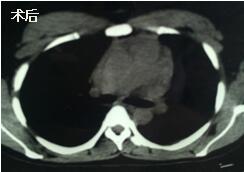

當看到病人癥狀緩解,復(fù)查胸部CT幾近完美,我們那種自豪感油然而生。偶爾去治愈,常常去幫助,總是去安慰,我們深知,小伙子的人生之路并不長,只能深深祈禱他在我們的治療下能走得更遠一些,能把剩下的日子走的更充實一些。而我們在能夠幫助人的時候,別一味地去安慰,永不言棄,是我們這一群胸外人堅貞的信念。